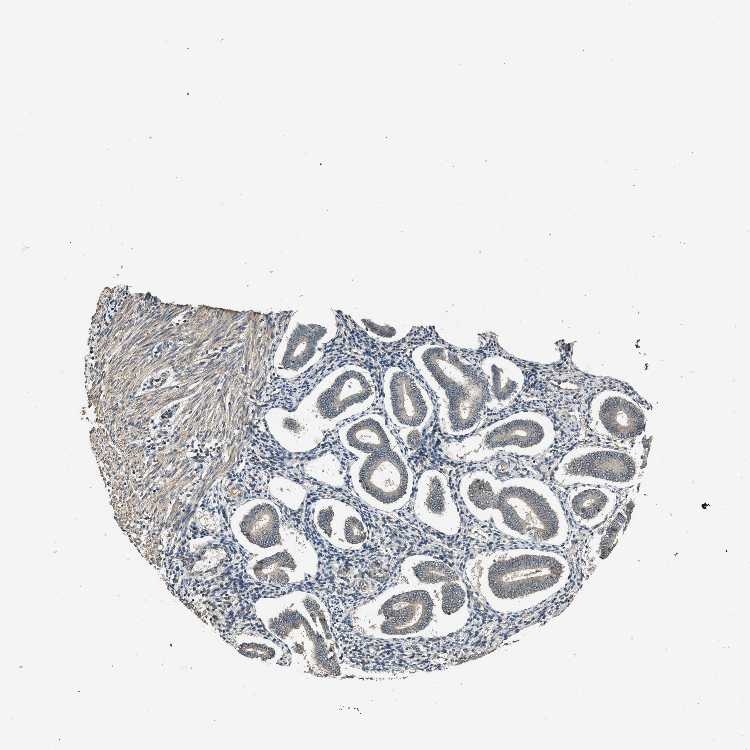

ENDOMETRIUM 1 - Antibody stainingi

Antibody staining in the annotated cell types in the current human tissue is reported as not detected, low, medium, or high, based on conventional immunohistochemistry profiling in selected tissues. This score is based on the combination of the staining intensity and fraction of stained cells.

Each image is clickable and will lead to virtual microscopy that enables deeper exploration of all samples and also displays staining intensity scores, fraction scores and subcellular localization as well as patient and tissue information for each sample.

Antibody HPA017177

Cells in endometrial stroma Not detected

Glandular cells Low